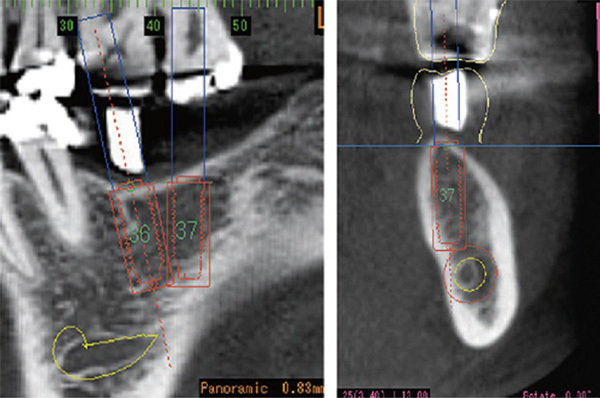

難症例でもインプラント治療を成功させるために、当院では最新のインプラントシュミレーションソフトiCATを用いてより精密な分析を行っています。

撮影させて頂いたCTを当院が導入している分析ソフトiCATを用いて、CTで得られた情報を3D化します。

構成された仮想空間にインプラントを仮置きして、シミュレーションすることによって、どの位置にインプラントを埋入すれば最適なのかを判断出来ます。

難症例でもインプラント治療を成功させるために当院では最新のインプラントシュミレーションソフトicatを用いてより精密な分析を行っています。

世界ではじめてicatシステムが可能にした「インプラント断面」により精度の高いインプラントシミュレーションを実現